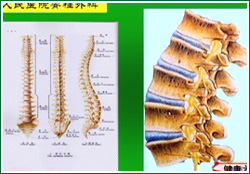

刘海鹰:来看一张片子,腰椎的作用主要是承重,从放大的腰椎图片中可以看到,腰椎分为5个椎体,中间有椎间盘,随着年龄的增长椎间盘的水分逐渐降低,吸水的能力下降,承受负荷的能力也下降,造成椎间隙的狭窄然后刺激后面的小关节增生、关节软骨发生磨损和炎性反应,逐渐产生腰椎退行性反应,最开始会发生椎间盘突出,然后是单个和多个阶段的椎管狭窄以及腰椎滑脱,最后发展为最严重的退行性脊柱侧弯。

王会民:腰椎的退化始于椎间盘,然后继发了黄韧带的肥厚、小关节的增生和内聚,最后就会导致椎管狭窄、腰椎滑脱甚至脊柱侧弯的发生。来看一张图,左边是一张正常的脊柱X光片,形状比较规则,右边是一张发生退行性改变后的脊柱X光片,产生了多处的骨赘并且椎间隙也不对称。

刘海鹰:腰椎神经根支配着下肢的感觉和运动,如图:神经根在受到压力的情况下就会产生相应所支配区域的疼痛。